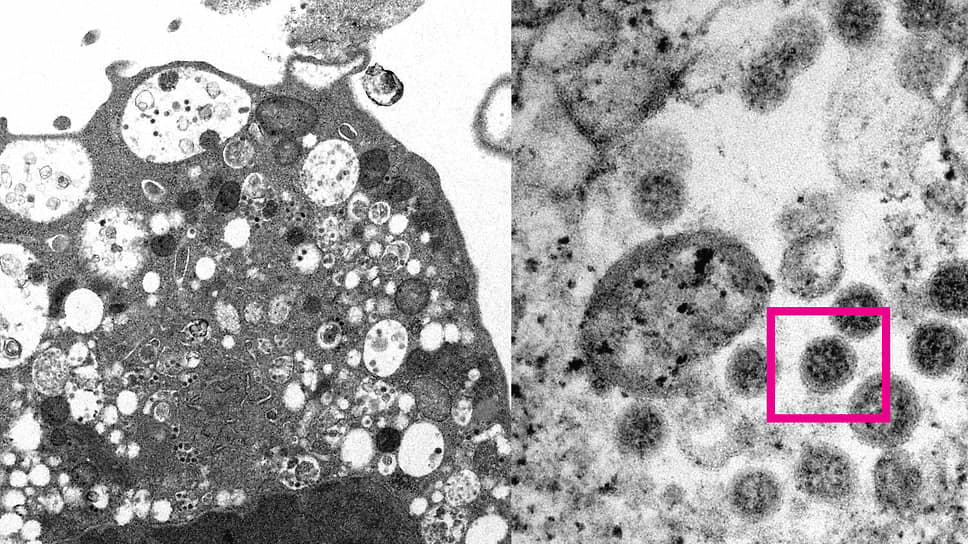

Университет Гонконга опубликовал изображение штамма коронавируса «омикрон», сделанное с помощью электронного микроскопа. Впервые этот штамм обнаружили в середине ноября в Ботсване. 6 декабря «омикрон» выявили у двух россиян, вернувшихся из ЮАР.

Изображение штамма коронавируса «омикрон»

Фото: med.hku.hk